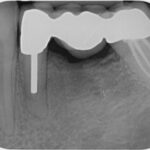

Ein weiterer wichtiger Störfaktor aus dem Zahn-Mund-Kieferbereich können sogenannte Restostitiden sein. Darunter versteht man meist klinisch stumme, lokal symptomfreie Entzündungen von Leerkieferbereichen, häufig als Langzeitfolge von Extraktionen entzündeter Zähne. Diese chronischen Entzündungen sind auf den zweidimensionalen Röntgenbildern kaum zu erkennen. Erst die dreidimensionale Bildgebung (DVT, CT) bringt hier diagnostische Klarheit.

Digitales 2-dimensionales Röntgenbild – Zahn mit Stift ohne Befund

3D-Röntgenbild (DVT) – deutliche sichtbarer ausgeprägter Entzündungsherd an der Wurzelspitze.